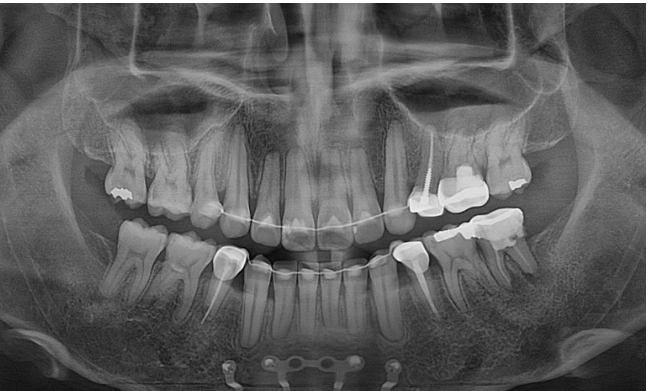

앞니 후방이동량이 큰만큼 앞니에 약간의 치근흡수가 보입니다.

치근평행도는 좋습니다.

어금니 쓰러짐은 인비절라인 발치교정의 가장 큰 난관입니다.

이 부분이 잘 컨트롤 되어야 엑스레이를 찍어봐도 결과가 좋다고 말할 수 있습니다.